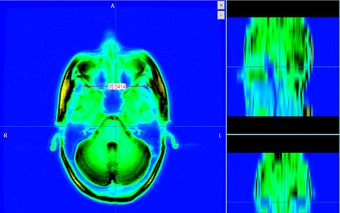

للمهنيين الطبيين والباحثين والطلاب لاستخدام تنسيق NIFTI و GIFTI و DICOM لعرض صورهم وتحليلها ومشاركتها لأغراض البحث وعرض صور DICOM و NIFTI لأنها توفر ميزات لعرض معلومات الصورة .

يوفر MRI Scalar ميزات مثل عارض الأطلس لمساعدة المستخدم في تحليل بيانات الصورة. يمكن للباحث والعالم الطبي استخدامه لإظهار هيكل المريض وتغييره لإجراء بحث طويل الأمد وتحديد موقع الورم أو الأمراض الأخرى. بالنسبة لطلاب الطب والباحثين ، فإنه يوفر القدرة على إنشاء نموذج ثلاثي الأبعاد لبيانات الصورة. p>